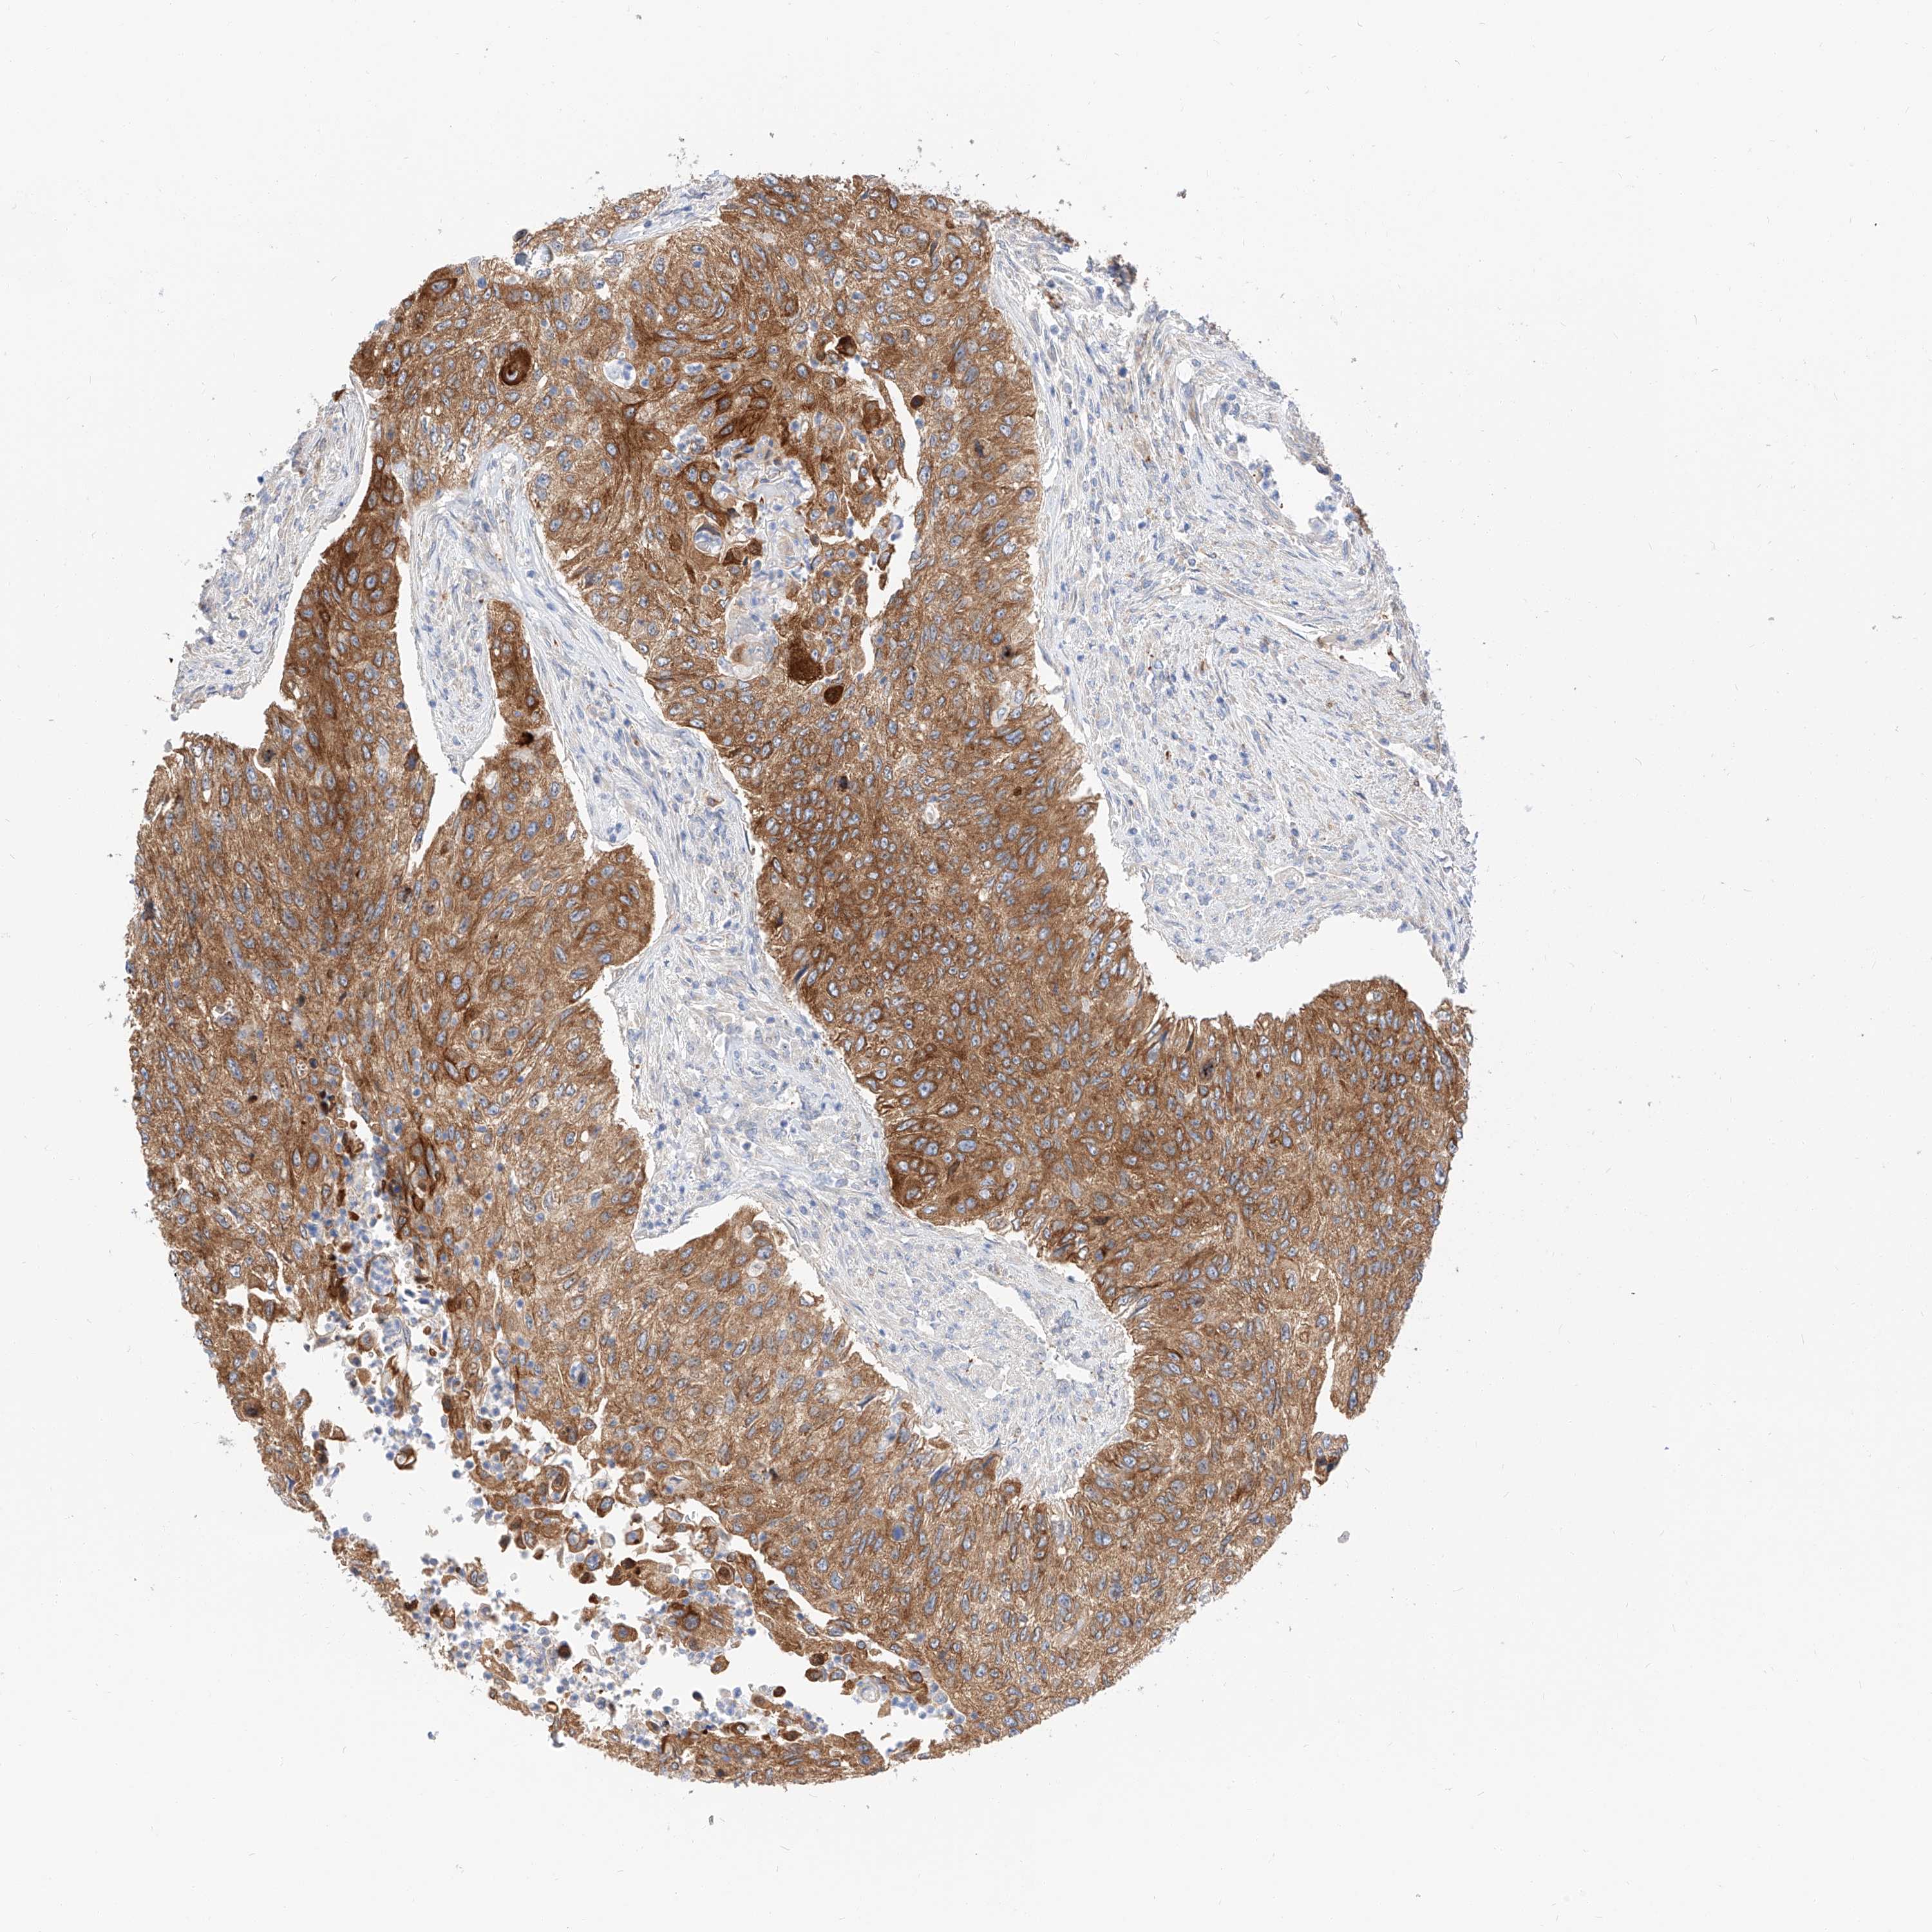

UROTHELIAL CANCER - Protein expressioni

A mouse-over function shows sample information and annotation data. Click on an image to view it in a full screen mode. Samples can be filtered based on level of antibody staining by selecting one or several of the following categories: high, medium, low and not detected. The assay and annotation is described here.

Note that samples used for immunohistochemistry by the Human Protein Atlas do not correspond to samples in the TCGA dataset.

Antibody stainingi

Antibody staining in the annotated cell types in the current human tissue is reported as not detected, low, medium, or high, based on conventional immunohistochemistry profiling in selected tissues. This score is based on the combination of the staining intensity and fraction of stained cells.

Each image is clickable and will lead to virtual microscopy that enables deeper exploration of all samples and also displays staining intensity scores, fraction scores and subcellular localization as well as patient and tissue information for each sample.

Antibody HPA029712

Antibody HPA029713

Staining

High

Medium

Low

Not detected

Intensity

Strong

Moderate

Weak

Negative

Quantity

>75%

75%-25%

<25%

None

Location

Nuclear

Cytoplasmic/membranous

Cytoplasmic/membranous,nuclear

Urothelial carcinoma, Low grade

Urothelial carcinoma, High grade